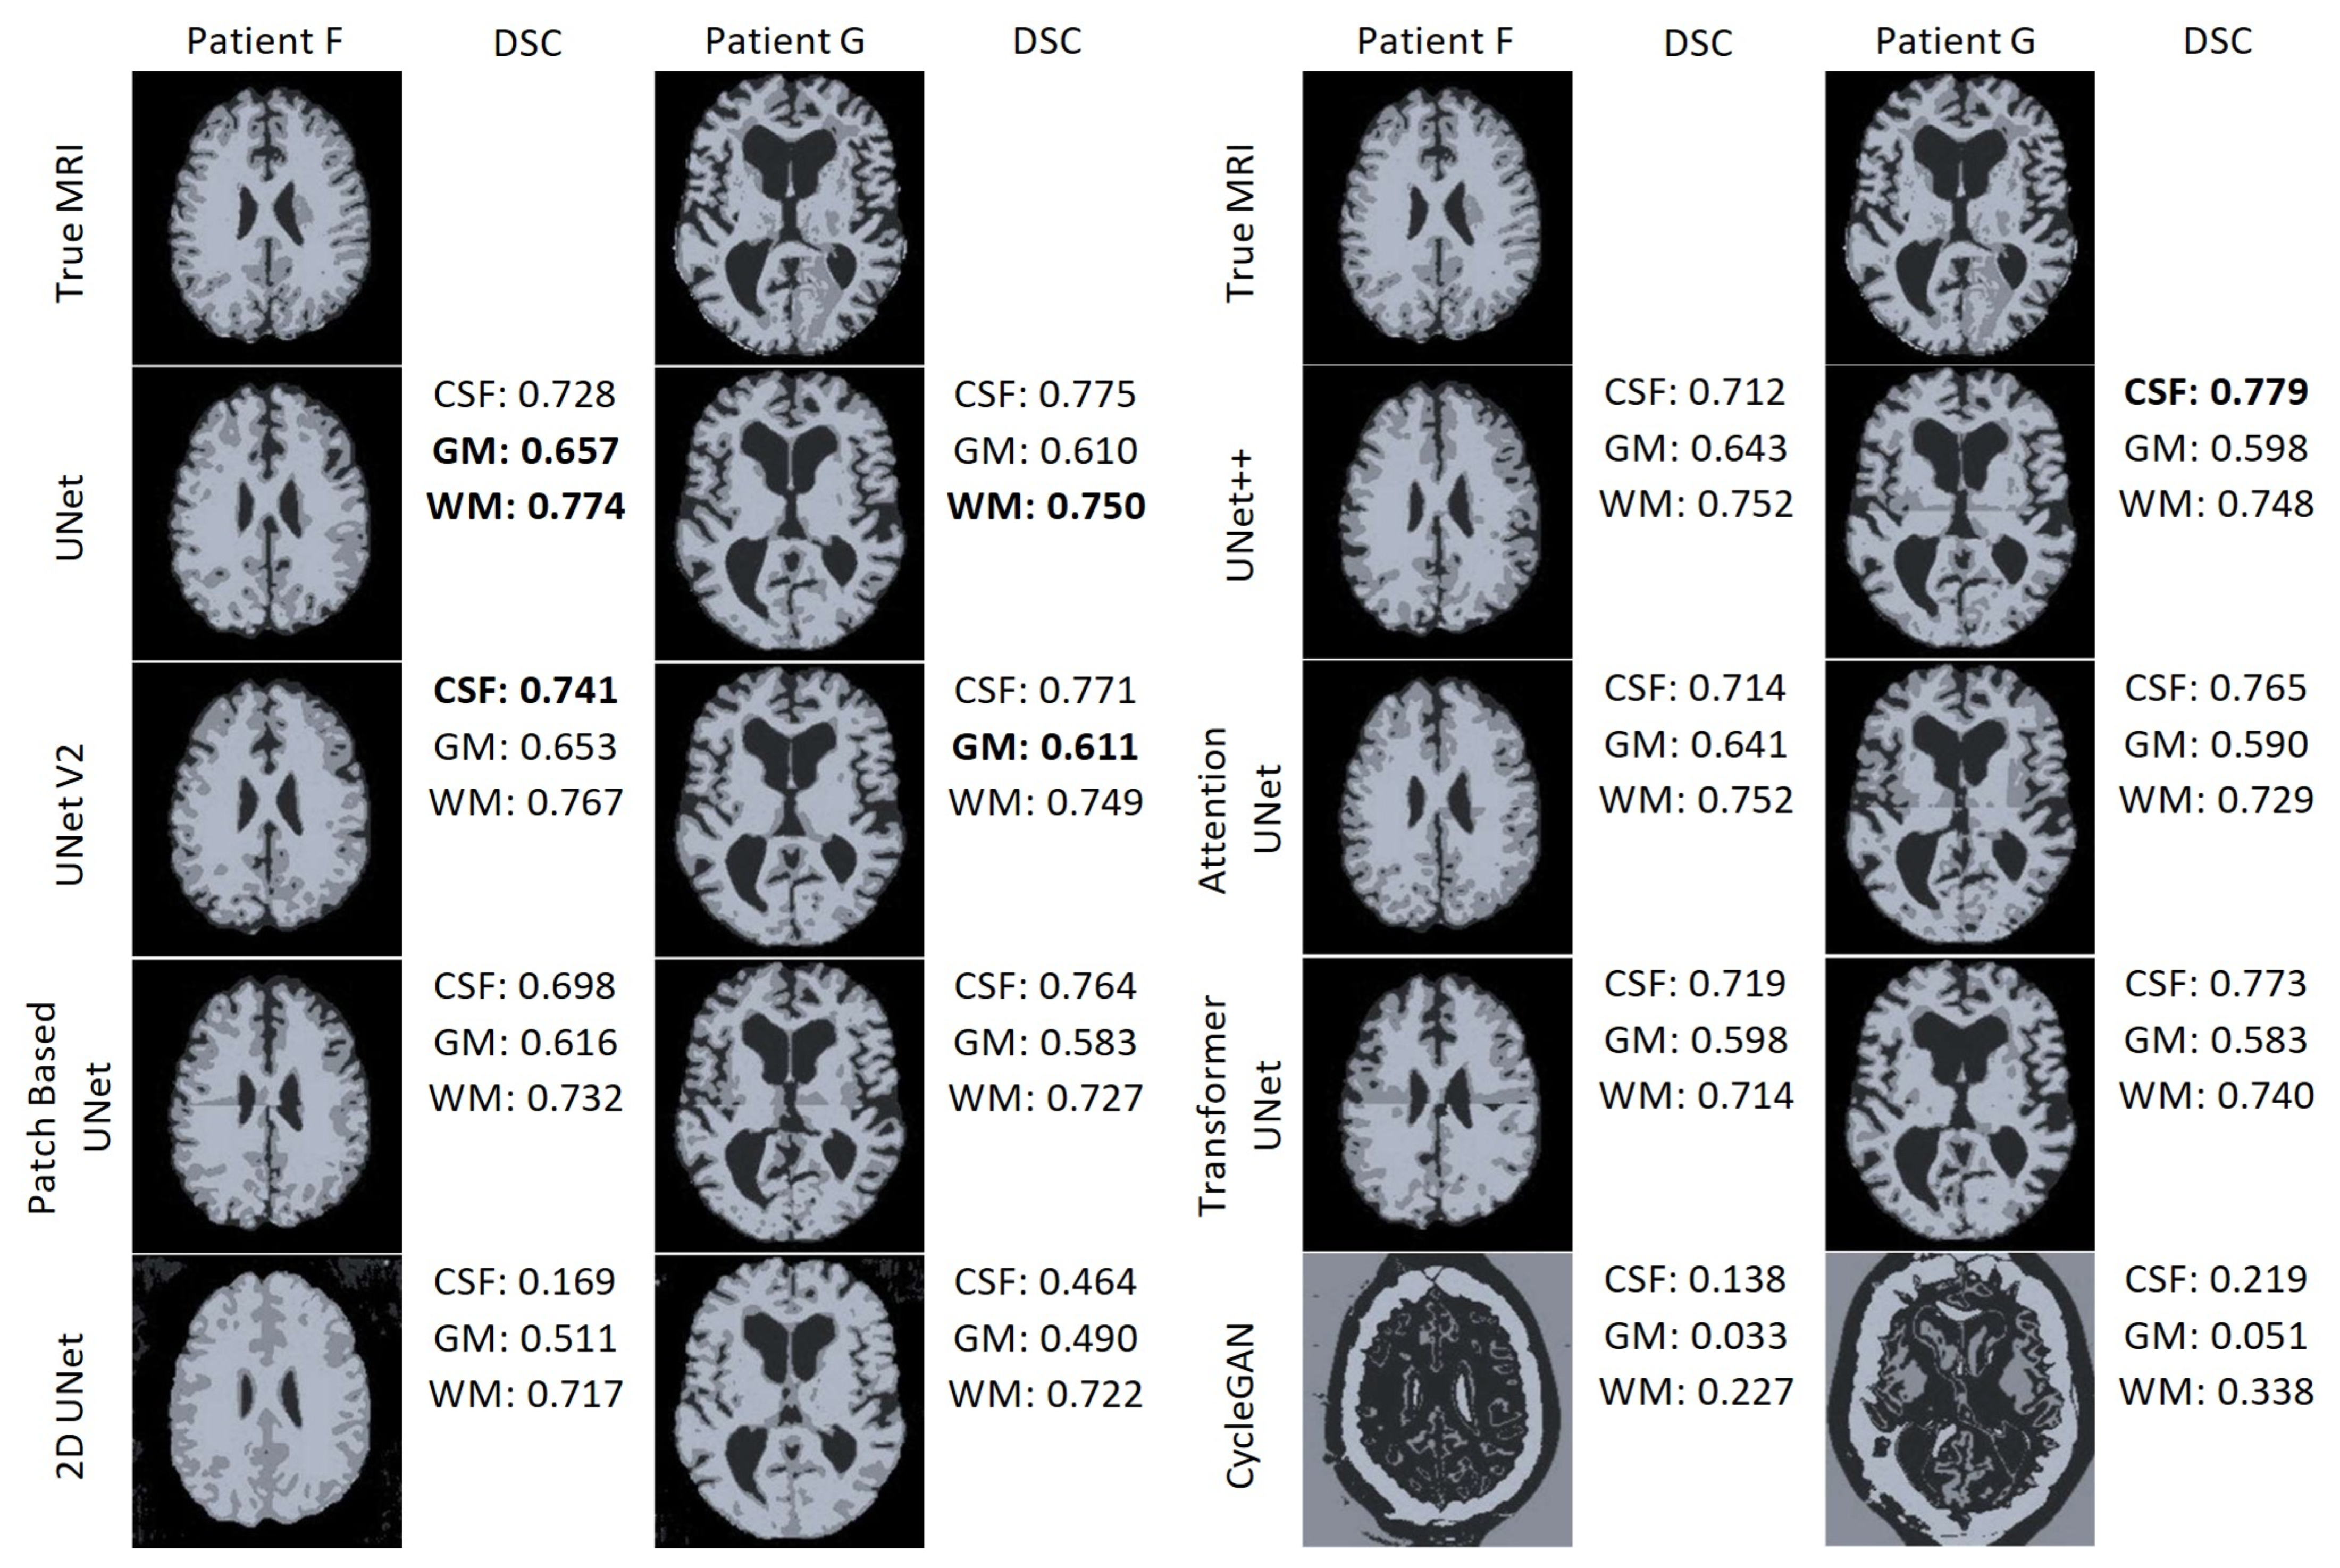

Figure 22 displays the results of the FAST algorithm applied to each MRI synthesis model and the true MRI for two patients. FAST did not perform well when applied to the CycleGAN results. Interestingly, the output classified most voxels as cerebrospinal fluid (CSF) for both patients, despite and unknown reason for this behaviour . Furthermore, in the patch-based models, it is evident that the FAST algorithm struggles to classify the regions around the edges of the patches. In the case of the 2D UNet synthetic MRI, the FAST model fails to identify CSF around the edge of the brain and instead misclassifies some areas outside the brain as CSF. Overall, UNet and UNet V2 demonstrate the best performance. UNet achieved the highest DSC for the GM and WM for Patient F, as well as the best WM DSC for Patient G. On the other hand, UNet V2 achieved the best WM DSC for Patient F, and the best GM DSC for patient G. UNet++ attained the highest DSC CSF score for Patient G.

Figure 22. Segmentation maps of the True MRI and Synthetic MRIs of Patient F and Patient G.